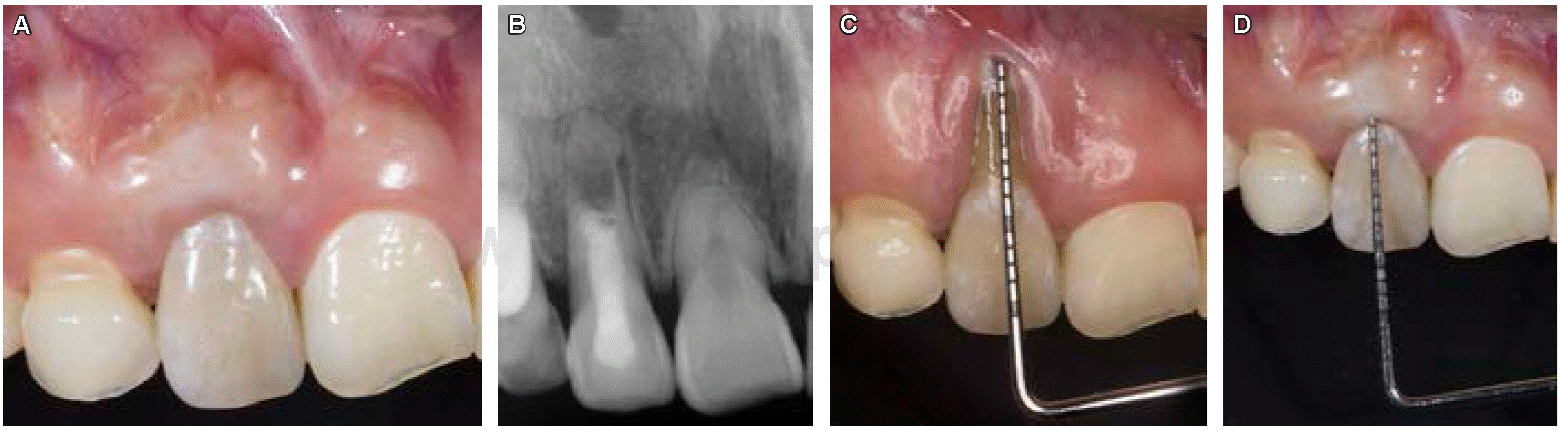

Paciente de sexo femenino de 20 años de edad que se presenta al consultorio dental para tratamiento de ortodoncia, pero se refiere a periodoncia por presentar inflamación y recesión gingival en el diente 12. Durante la evaluación periodontal inicial se realizó sondeo periodontal, observando inflamación, exudado purulento y deformidad mucogingival por vestibular (recesión gingival). Al interrogatorio la paciente no refiere antecedentes personales patológicos, por lo que se considera paciente aparentemente sana. El diagnóstico periodontal fue gingivitis inducida por placa bacteriana y recesión gingival clase I de Miller en el órgano dentario 12. Se tomaron radiografías periapicales para completar los auxiliares de diagnóstico (Figura 1).

Al realizar pruebas de vitalidad pulpar y de percusión el órgano dentario 12 no responde, clínicamente se observa cambio de coloración en la corona además de recesión gingival, al examen radiográfico se aprecia ápice abierto y lesión radiolúcida a nivel periapical; basados en los hallazgos clínicos y radiográficos, el diagnóstico fue necrosis pulpar con periodontitis apical asintomática, por lo que el tratamiento es apicoformación con MTA (Figura 2A).

Figura 2: A) Radiografía periapical preoperatoria. B) Resultados de la fase I periodontal. C) Procedimiento quirúrgico para la eliminación de canino retenido y apreciación del ápice inmaduro. D) Radiografía final del tratamiento de conductos.

Figura 4: A) Fotografía final, revisión dos años después. B) Radiografía periapical a dos años de haber concluido el tratamiento. C) Sondeo periodontal inicial. D) Sondeo periodontal final.

Al sondeo periodontal no se encontró bolsa perio dontal y se pudo corroborar la inserción adecuada del injerto, comparando clínicamente el sondeo periodon tal y final (Figuras 4CyD).